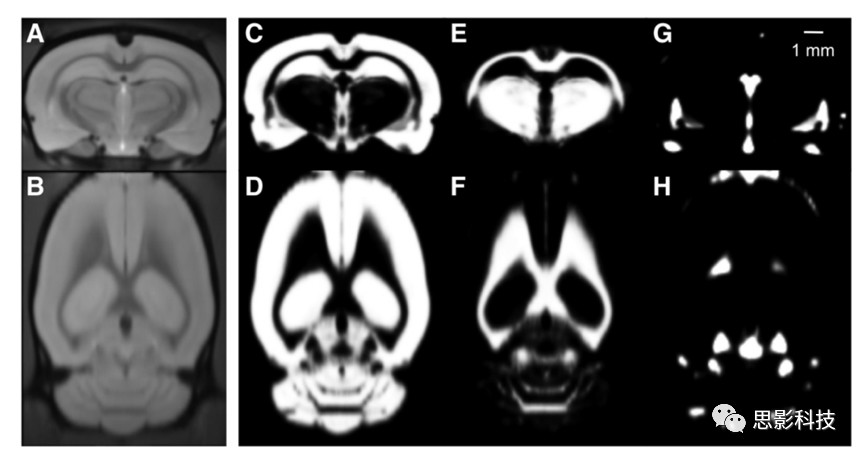

灰白質(zhì)分析圖例